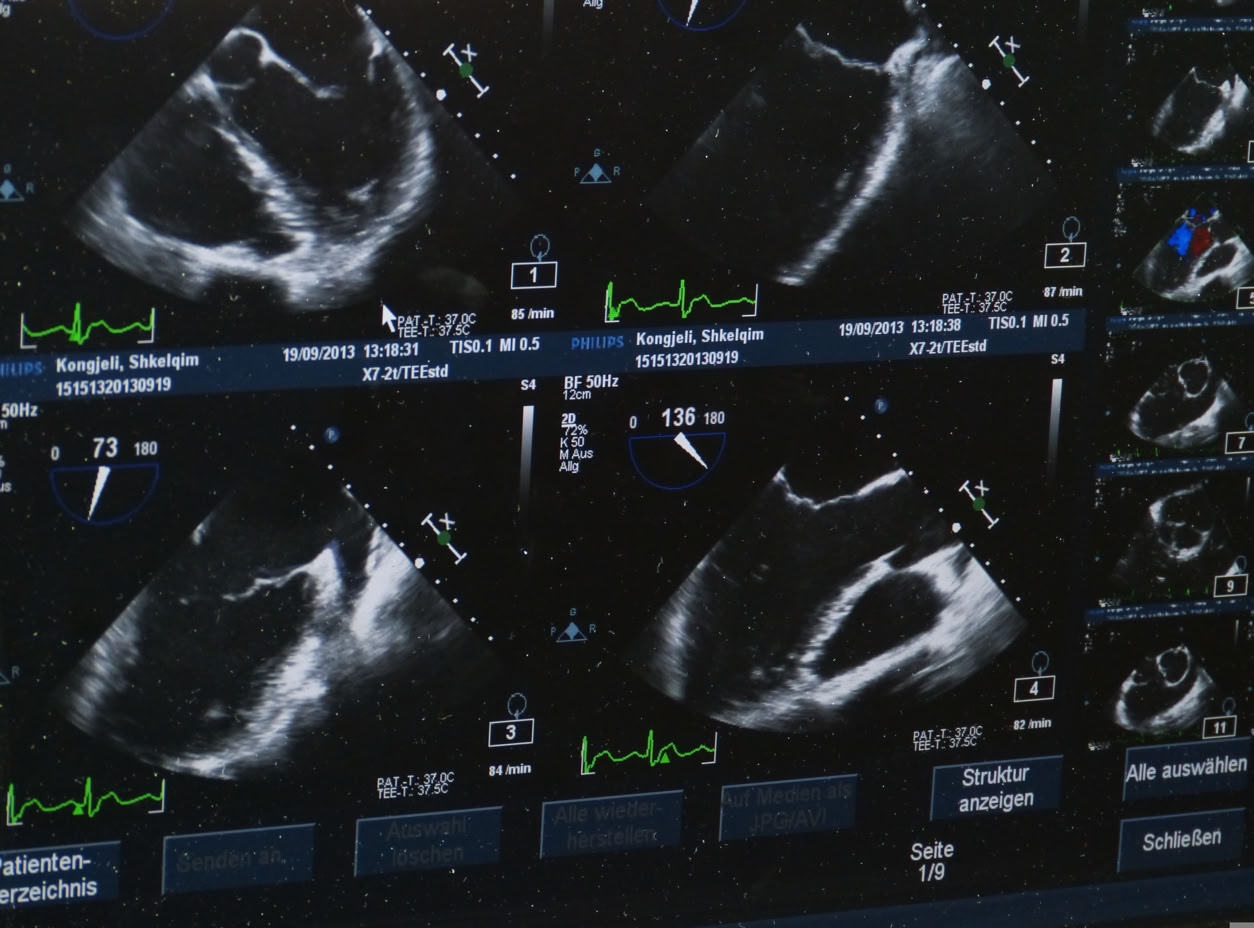

- Echokardiographie mit Duplexsonographie und Strain-Messung

Echokardiographie Untersuchung, Kardiologie Herrsching

Echokardiogrpahie